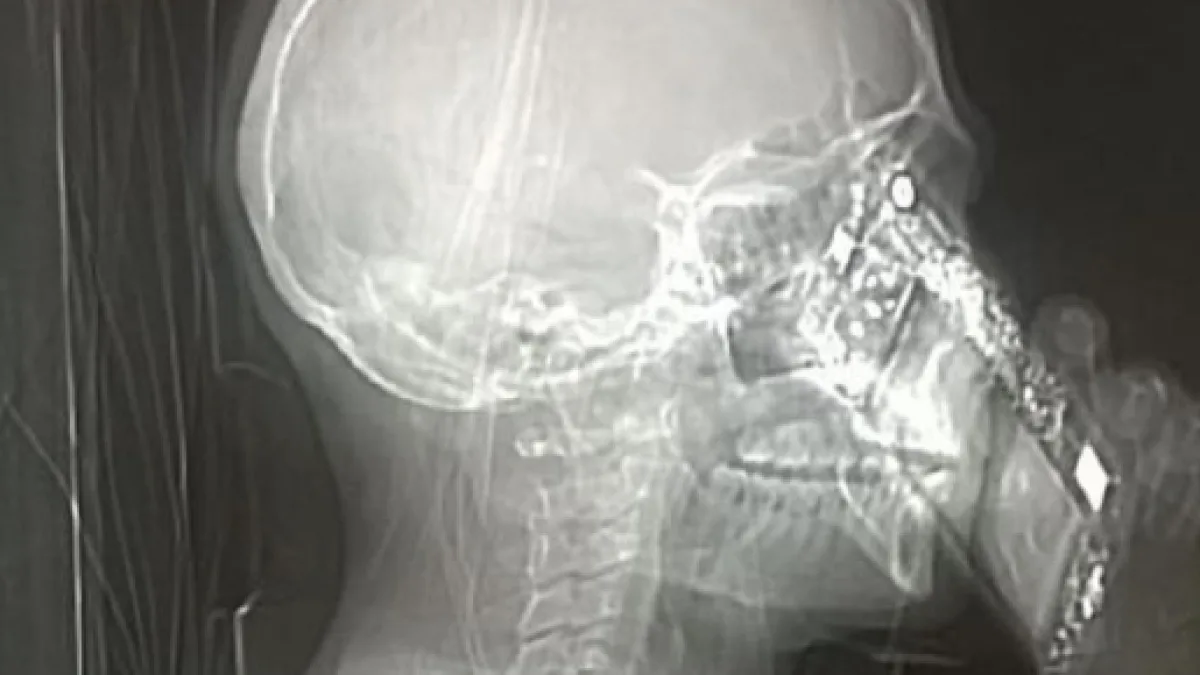

Pochi giorni fa, al Cardarelli di Napoli, si è presentata una signora che lamentava dei forti e continui mal di testa. Dopo molti accertamenti e con il sospetto che la donna soffrisse di cefalea, i medici hanno preso la decisione di sottoporla ad una Tac. La procedura di routine dell'esame tomografico è nota quasi a tutti: bisogna togliere ogni tipo di oggetto metallico o simili (collane, orecchini, piercing, telefoni ecc.) per evitare che questi compromettano l'immagine risultante dalla Tomografia.

La cosa che, al contrario, ha lasciato basiti i medici dell'ospedale napoletano è stata che la donna abbia deciso di rispondere al proprio telefonino, compromettendo la foto registrata dalla tac. Anche la giustificazione data dalla signora ha destato parecchio scalpore: alla domanda dei medici la donna si è giustificata dicendo di avere avuto un lapsus.

Molti utenti del web e lo stesso staff del Cardarelli ha ipotizzato, di conseguenza, che potrebbe essere stato proprio l'eccessivo uso del cellulare la causa dei frequenti mal di testa della donna. Infine, i medici hanno deciso di diffondere la foto della tac per chiarire quanto il comportamento della signora possa essere sbagliato e pericoloso. Lo stesso primario Mario Muto ha dichiarato, a Tgcom, che la situazione sembrava davvero paradossale e che i tecnici hanno provveduto ad interrompere subito l'esame.